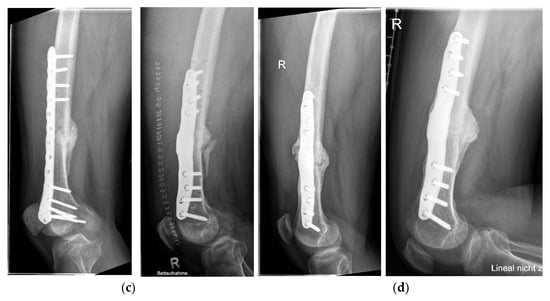

Long-Term Evaluation of Bone Healing Monitoring Using an Instrumented Plate with Measurement Sensors (Smart Implant) over 10 Years

by Arndt P. Schulz, Birgitt Kowald, Matthias Münch, Klaus Seide, Nils Weinrich, Tobias Barth and Benjamin Kienast

Sensors 2025, 25(18), 5779; https://doi.org/10.3390/s25185779 - 16 Sep 2025

A total of 66 smart implants were included. As a measure of bony stability, the relative elastic compliance of the osteosynthesis was determined from the gradient between the applied external load and the measured implant load over the entire healing process. The healing [...] Read more.

A total of 66 smart implants were included. As a measure of bony stability, the relative elastic compliance of the osteosynthesis was determined from the gradient between the applied external load and the measured implant load over the entire healing process. The healing process of non-unions of the femur with a smart implant was tracked by telemetric measurements over a timespan of up to 10 years. The measurements of the longest healing process show a very slow but constant decrease in force transmission over the implant, radiological findings over 10 years show corresponding consolidation until bony healing. The use of a telemetrically instrumented bone plate, a so-called smart implant, to monitor the healing process is a successful procedure to support the clinician in his decision to take further surgical measures or to wait until healing occurs. Full article